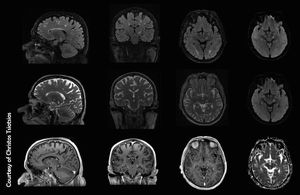

High-resolution, multiparametric MR Imaging of brain metastasis (typical ring enhancing lesion), based on volumetric acquisitions (3D T2, 3D T2 FLAIR & 3D T1 post contrast are shown here) and SS-EPI DWI with b0 (not shown here), b500, b1000 and ADC map